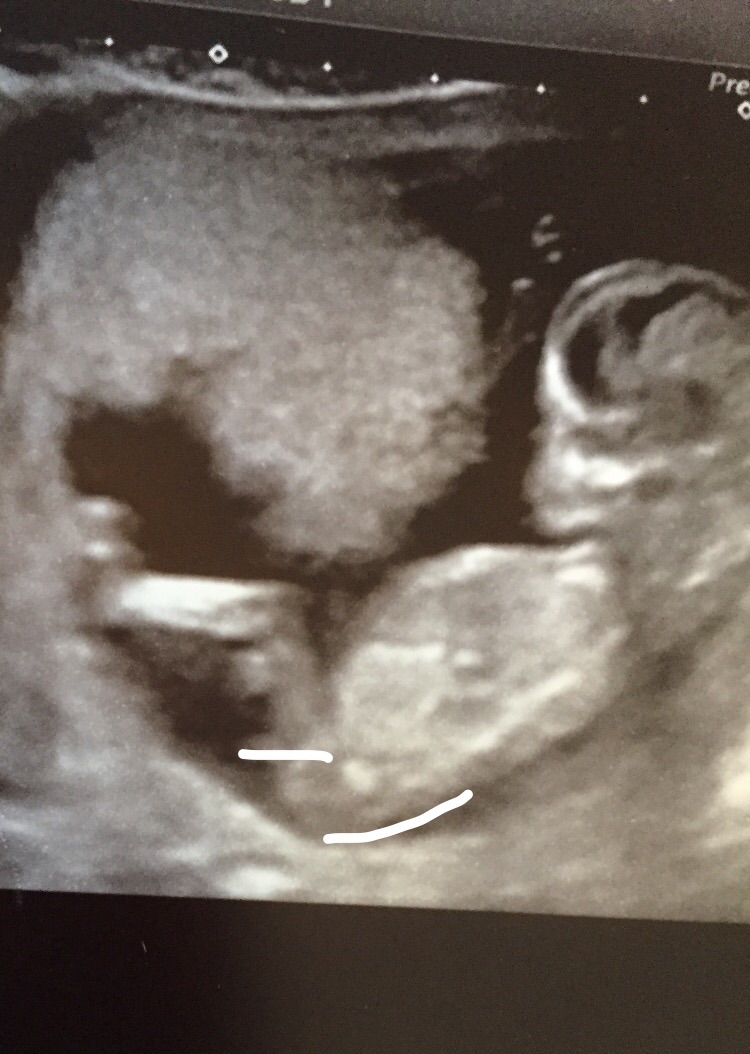

Hi this is my scan 12+6 feel free to guess Attachment 25114Attachment 25115

I think might be a boy

i think boy xxx

Boy

60/40 for girl.

Not clear enough sorry!

Boy guess.

Maaayyybe boy? GL